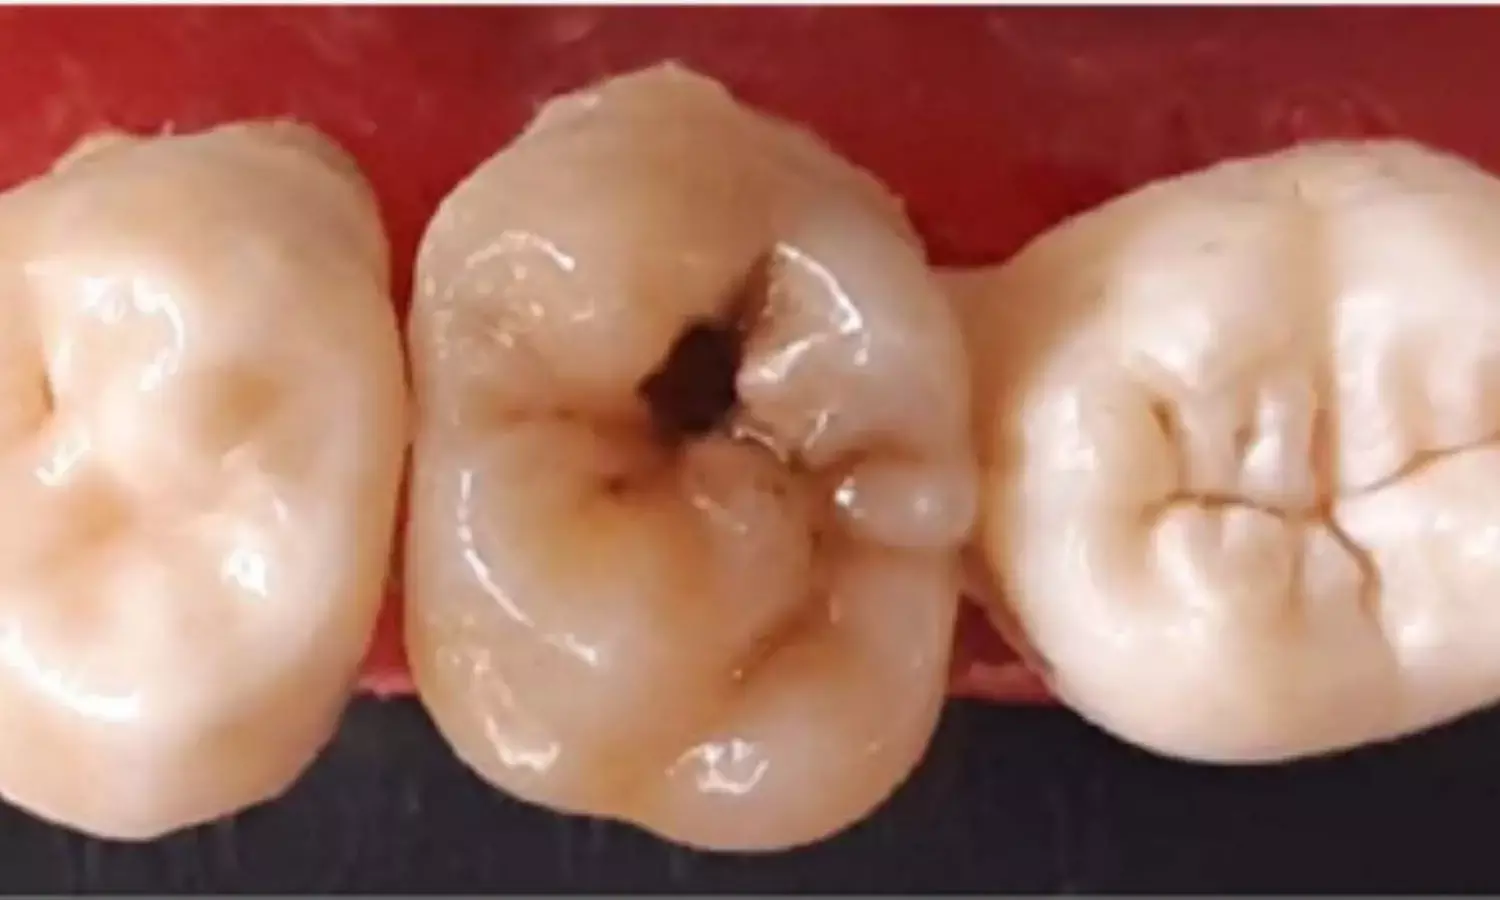

Kuwait: Researchers have found in a new study that both fluoride varnish (FV) and glass ionomer cement (GIC) sealants effectively protect newly erupted permanent molars from occlusal caries. While FV showed slightly higher plaque accumulation, overall caries prevention was comparable. Clinicians can therefore choose either option based on practical factors, patient preference, and available resources without compromising clinical outcomes.

Occlusal caries prevention in newly erupted permanent molars is a major focus in pediatric dentistry, as these teeth are highly susceptible during early eruption. Fluoride varnish and glass ionomer cement sealants are commonly used preventive measures, but their comparative benefits have remained uncertain. The new systematic review and meta-analysis published in the Cureus Journal of Medical Science

provides updated evidence on their relative effectiveness.